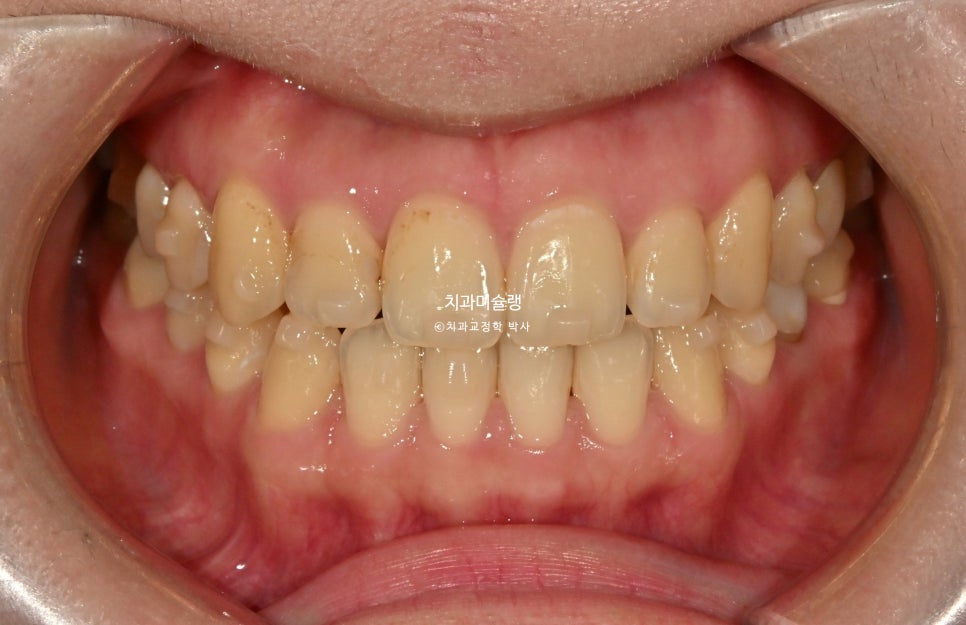

중심선이 맞아졌으며 앞니 교합이 개선되었습니다. 기울어져있던 앞니 치축이 똑바로 개선되었습니다.

또한 내려와있고 튀어나와있던 송곳니는 제자리를 찾았습니다.

앞니 배열이 개선되면서 단차가 사라져, 이제는 삭제 없이 무삭제로 라미네이트가 가능합니다.

작은어금니에서 작은어금니까지, 앞니 8개에 무삭제라미네이트 젤라미 부착 모습입니다.

잇몸쪽에서 치아 끝단으로 갈수록 음영이 자연스럽게 지는것이 무삭제 라미네이트의 강점 입니다.

어두워보이던 치아가 환해졌습니다.

스마일라인도 아랫입술과 평행하게 회복되었습니다.

단지 색깔의 변화는 아니고 두께감과 배열 개선의 효과도 큽니다.